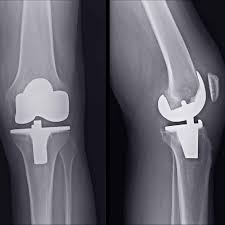

At Varunam Super Speciality Hospital, various knee replacement options are offered to match individual needs and joint conditions. These include:

• Partial knee replacement for targeted damage

• Total knee replacement for widespread arthritis

• Revision knee replacement when previous implants need adjustment

Dr. Utsav Agrawal evaluates each patient’s condition with detailed assessment and imaging to recommend the most suitable option. This personalised approach ensures optimal outcomes and long-term joint performance.